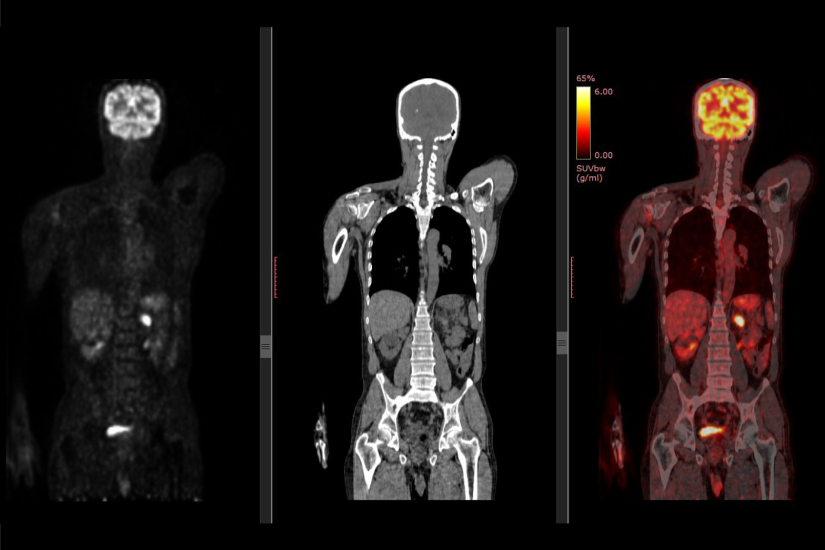

Prin incorporarea in echipamentul PET a unui computer tomograf (CT) se obtine un echipament hibrid PET-CT. Acesta prezinta avantajul obtinerii printr-o singura examinare a unei imagini care permite localizarea cu precizie a leziunilor active metabolic identificate. In imaginea de mai sus, in stanga este examinarea PET, in timp ce imaginea centrala este o scanare CT, iar imaginea din dreapta este obtinuta prin suprapunerea celor doua imagini.